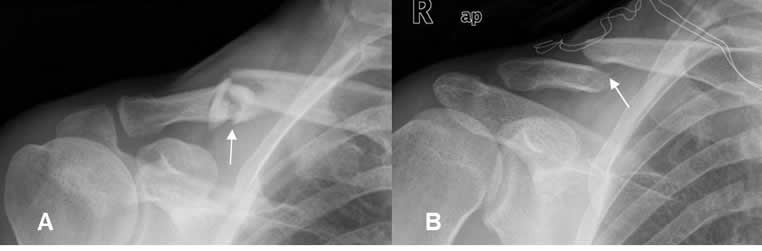

Fig 62. Fractura de clavícula.

A: Rx AP. Fractura conminuta del tercio medio, con leve angulación superior.

B: Rx AP. Fractura cabalgada del tercio medio, con desplazamiento superior del extremo proximal y diastasis de la articulación acromioclavicular.